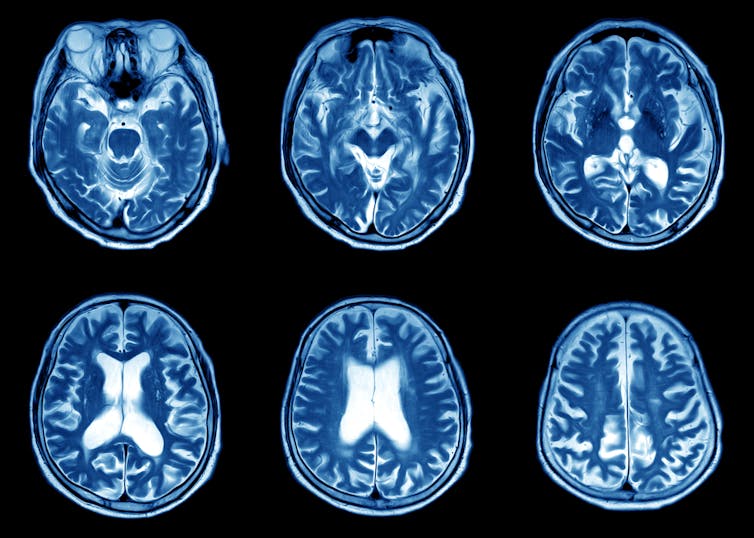

Magnetic resonance imaging (MRI)

MRI uses a combination of a powerful cylindrical magnet and radiofrequency waves to generate an image of the body. It’s quite loud and patients must be wearing suitable hearing protection devices such as earplugs or headphones (where relaxing music can be listened to).

Patients normally lie within the magnet cylinder, and a frame (which works like an antennae) is placed around the body area needing to be imaged, as close as possible, so the maximum possible signal can be detected in order to reconstruct highly detailed images.

Our body contains hydrogen, so a radiofrequency is transmitted into the body at the frequency that will cause hydrogen atoms to oscillate. When the radiofrequency is switched off, the hydrogen atoms continue to oscillate and the frequency of this oscillation is detected by the frame or antennae.

The radiofrequency causes a voltage signal in the antennae, which is identified as an electrical signal. This is then digitised and an image is reconstructed using complex mathematical calculations.

Safety is paramount for patients having an MRI scan, and all patients must complete a safety questionnaire first to ensure they’re compatible with the imaging environment. The safety questionnaire asks if patients have any implanted metal objects such as pacemakers or infusion pumps or similar medical devices. This is because certain metal objects can cause harm to patients or staff if they enter the MRI environment because of the powerful magnet.

The most common application of MRI is imaging the brain with conditions that relate to neurology or neurosurgery.